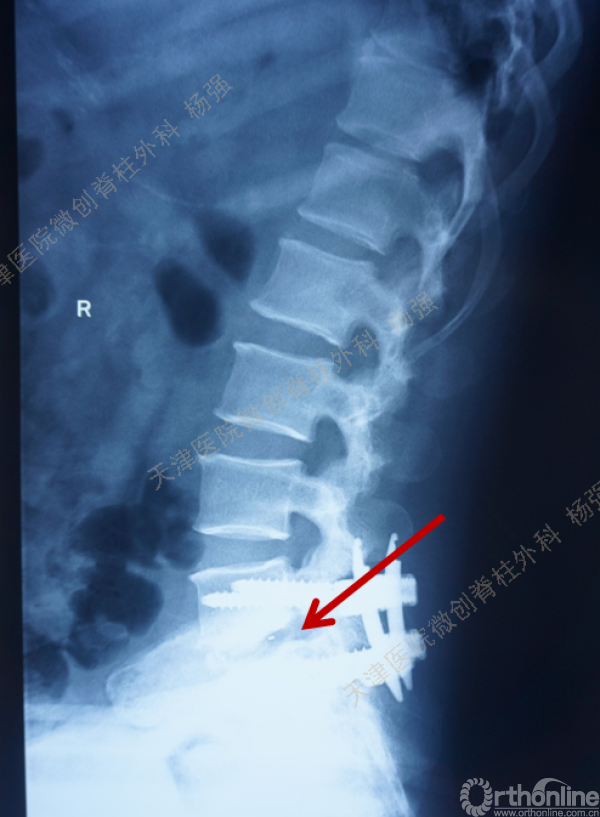

腰5椎体前滑脱I-II°,峡部裂,动力位显示腰5-骶1节段明显失稳

CT、MRI示:腰5椎体前滑脱,腰5/骶1水平间盘突出,腰5双侧椎弓峡部裂